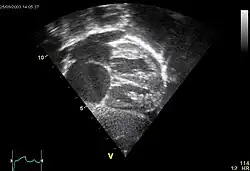

Echocardiography

In transthoracic echocardiography, an atrial septal defect may be seen on color flow imaging as a jet of blood from the left atrium to the right atrium.

If agitated saline is injected into a peripheral vein during echocardiography, small air bubbles can be seen on echocardiographic imaging. Bubbles traveling across an ASD may be seen either at rest or during a cough. (Bubbles only flow from right atrium to left atrium if the right atrial pressure is greater than left atrial). Because better visualization of the atria is achieved with transesophageal echocardiography, this test may be performed in individuals with a suspected ASD which is not visualized on transthoracic imaging. Newer techniques to visualize these defects involve intracardiac imaging with special catheters typically placed in the venous system and advanced to the level of the heart. This type of imaging is becoming more common and involves only mild sedation for the patient typically.

If the individual has adequate echocardiographic windows, use of the echocardiogram to measure the cardiac output of the left ventricle and the right ventricle independently is possible. In this way, the shunt fraction can be estimated using echocardiography.